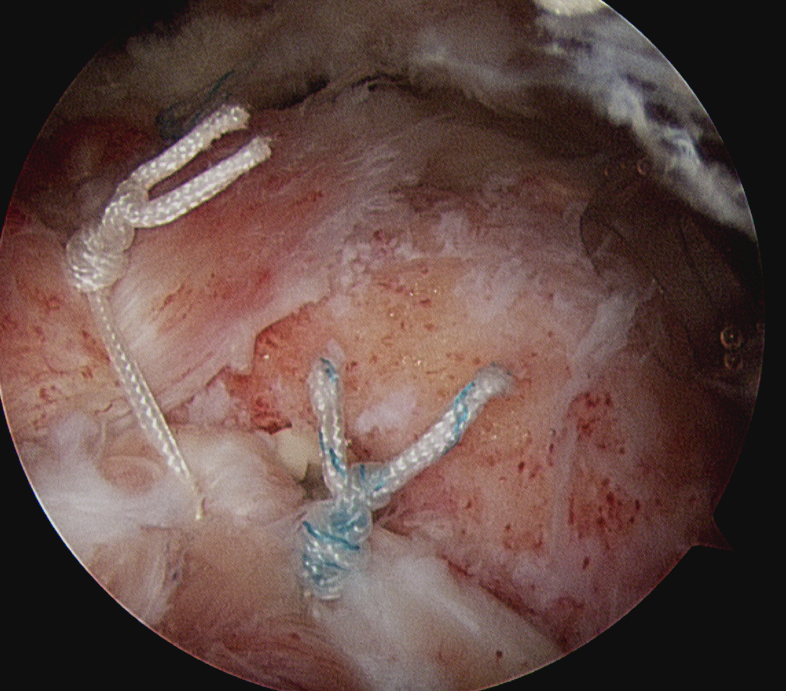

Vumedi arthroscopic repair of massive rotator cuff tear video

Subacromial arthroscopy

- leave coracoarcomial ligament intact to prevent humeral head escape

- subscapularis repair

- mobilize supraspinatus and infraspinatus above and below glenoid

- repair infraspinatus above equator

- repair supraspinatus as able

- typically leave area of humeral head exposed

Margin convergence sutures

Release infraspinatus tendon posteriorly and assess mobility

Repair infraspinatus with a combination of margin convergence and posterior suture anchors onto posterior greater tuberosity

True partial repair of the rotator cuff with exposed triangle of greater tuberosity